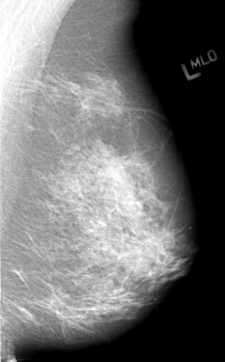

Volume: cancer_01 Case: B-3012-1

B_3012_1.LEFT_MLO

LEFT_MLO LINES 4336 PIXELS_PER_LINE 2696 BITS_PER_PIXEL 12 RESOLUTION 50 NON_OVERLAY

FILE: B_3012_1.RIGHT_MLO.OVERLAY

TOTAL_ABNORMALITIES 1

ABNORMALITY 1

LESION_TYPE MASS SHAPE IRREGULAR MARGINS SPICULATED

ASSESSMENT 4

SUBTLETY 3

PATHOLOGY MALIGNANT

TOTAL_OUTLINES 1

BOUNDARY